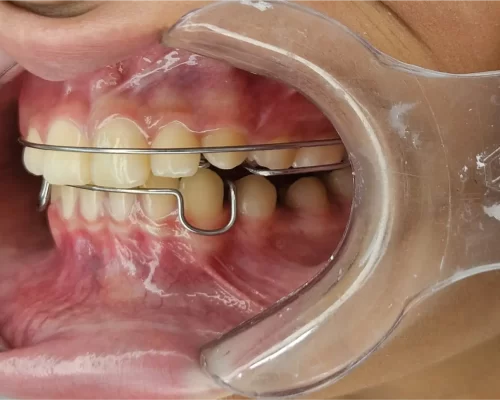

Ortopedia & Ortodontia

Alinhadores, aparelhos estéticos, aparelhos ortopédico e convencional.

Desconforto com aparelho mal ajustado